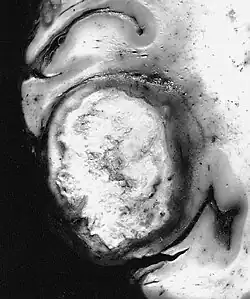

![]() Examen macroscópico. Esta variedad gigantocelular del glioblastoma muestra una masa sólida y compacta que radiológicamente podría confundirse con un carcinoma metastásico. | ||